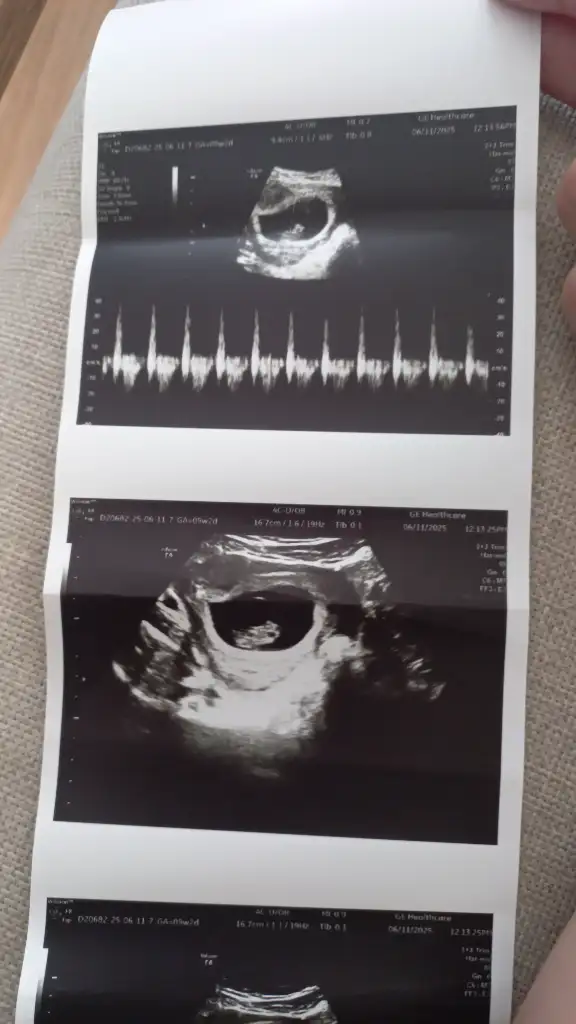

Kızlar benim bebişim de 9+0 da 😍 kese önceli haftalarsa yusyuvarlaktı şimdi şekli değişmiş. Doktor kız gibi tahmin ediyorum dedi. Sizde hislerinizi söyler misiniz 😍

• IMG_8812.webp

IMG_8812.webp

31,8 KB · Görüntüleme: 65